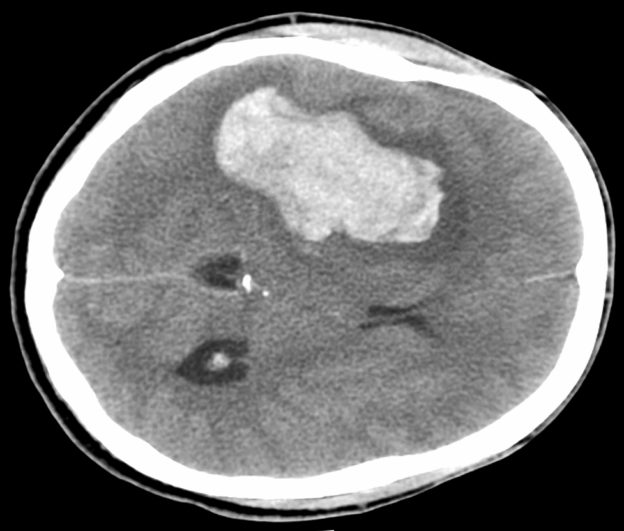

Contributor: Alec Coston, MD Case Report Summary: A 17-year-old female involved in a motor vehicle collision presented to a rural emergency facility via personally operated vehicle. During workup and initial CT scan, the patient began rapidly decompensating with CT revealing a 1.5cm epidural hematoma with 7mm of midline shift. The patient went from being able to walk and talk to being obtunded with a blown left pupil and unresponsive. Following intubation, the patient was being prepared for transport but potential delays required immediate emergency evacuation of the hematoma via a Burr Hole. A traditional Burr Drill was not immediately available at the facility, so an improvised Burr Drill using an Intraosseous (IO) drill was used. 35mL of blood was removed from the hematoma and the patient immediately improved from a GCS of 3 to GCS of 8. The patient was transferred to a higher level of care facility, extubated the following day, and made a full neurological recovery. Educational Pearls: What is an epidural hematoma? An epidural hematoma is a collection of blood between the dura mater (outermost layer of the meninges) and the skull, whereas a subdural hematoma is a collection of blood between the dura mater and arachnoid mater. Both can be life threatening depending on location and size. Epidural hematomas tend to be arterial, and are typically secondary to trauma and can rapidly expand, but with timely recognition and evacuation of the bleed, favorable outcomes are often possible. What are typical intracranial pressures and at what levels do they become pathologic? Typical intracranial pressure (ICP) varies by age, but past infancy and early childhood, adolescents and adults have a value typically between 8-15mmHg. Values exceeding 20mmHg become pathologic and rise exponentially with increased volume. Initial symptoms may include headache, nausea, and vomiting, but with increased pressures may progress to more life threatening symptoms such as loss of consciousness, cranial nerve palsies, pupillary constriction or dilation (sign of herniation), and respiratory irregularities. What is the takeaway in timing of epidural hematomas? Older studies show that evacuation of a hematoma with lateralizing features before the two hour mark of coma symptom onset is correlated with decreased mortality (ranging from 15-17%), but beyond 2 hours the mortality increases to well over 50%. Though mortality statistics have grown more variable, early targeted evacuation of epidural hematomas still remains critical for improved patient outcomes. In austere conditions with limited resources, improvisation with interosseous drills and needles can improve patient outcomes and achieve the target therapy for epidural hematomas. References Haselsberger K, Pucher R, Auer LM. Prognosis after acute subdural or epidural haemorrhage. Acta Neurochir (Wien). 1988;90(3-4):111-116. doi:10.1007/BF01560563 Hawryluk GWJ, Nielson JL, Huie JR, et al. Analysis of Normal High-Frequency Intracranial Pressure Values and Treatment Threshold in Neurocritical Care Patients: Insights into Normal Values and a Potential Treatment Threshold. JAMA Neurol. 2020;77(9):1150-1158. doi:10.1001/jamaneurol.2020.1310 Pisică D, Volovici V, Yue JK, et al. Clinical and Imaging Characteristics, Care Pathways, and Outcomes of Traumatic Epidural Hematomas: A Collaborative European NeuroTrauma Effectiveness Research in Traumatic Brain Injury Study. Neurosurgery. 2024;95(5):986-999. doi:10.1227/neu.0000000000002982 Summarized by Dan Orbidan, OMS2 | Edited by Dan Orbidan and Jorge Chalit, OMS4 Donate: https://emergencymedicalminute.org/donate/